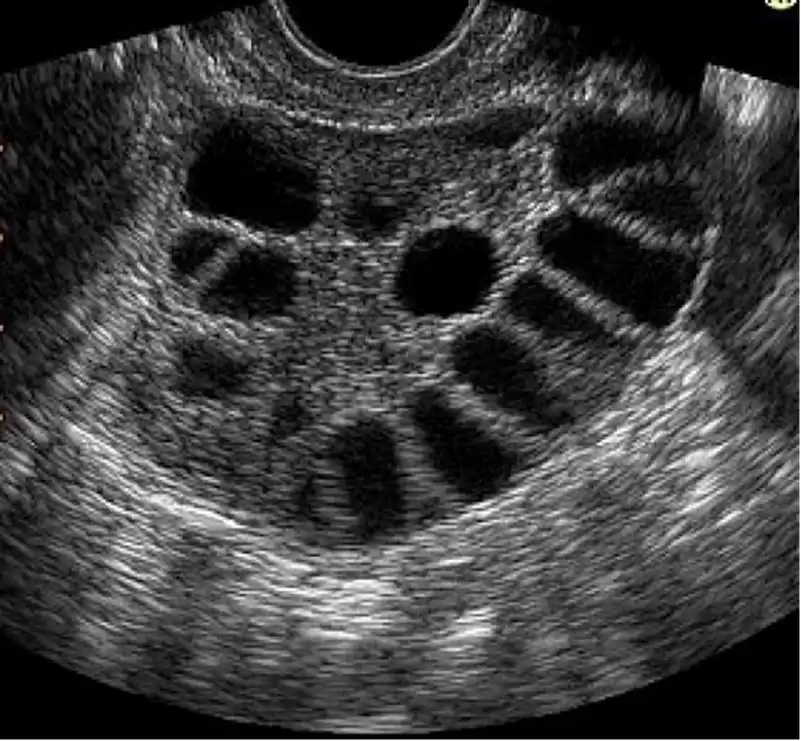

Το Σύνδρομο Πολυκυστικών Ωοθηκών (PCOS) είναι η πιο συχνή ορμονική διαταραχή σε γυναίκες αναπαραγωγικής ηλικίας, η οποία εμφανίζεται σε ποσοστό έως και 10%. Χαρακτηρίζεται από υπερπαραγωγή ανδρογόνων, των ανδρικών ορμονών, διαταραχές της εμμήνου ρύσεως όταν δεν εμφανίζεται ωορρηξία και διευρυμένες ωοθήκες που περιέχουν πολλαπλά μικρά θυλάκια (πολυκυστικές ωοθήκες).

- Υπερηχογραφικός έλεγχος ότι έχετε πολυκυστικές ωοθήκες.